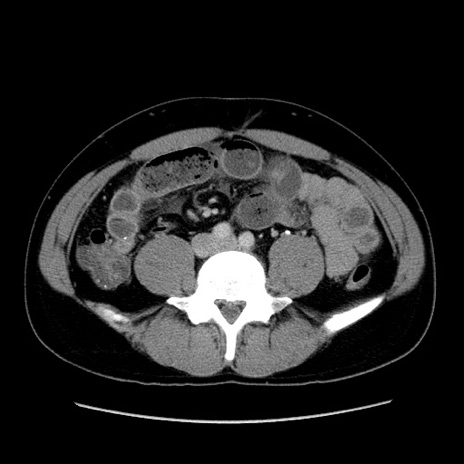

症例4(横断像)

【症例】30歳代男性

【主訴】腹痛、嘔吐

【現病歴】昨晩から突然の腹痛あり、その後嘔吐、軟便も出現。腹痛が改善しないため救急搬送となる。2日前にしめ鯖の食事歴あり。

【身体所見】意識清明、苦悶様、BP 135/90mmHg、BT 35.7℃、腹部:平坦、やや硬、心窩部〜臍部に自発痛、圧痛あり、筋性防御+、反跳痛-

【データ】WBC 8100、CRP 0.57